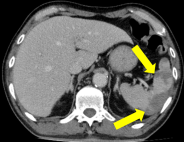

65岁女性,既往心房颤动、脑梗死,20小时前进食后出现剧烈腹痛,并有便血,

CTA示SMA栓塞。在Straub导管吸栓后,利用腹腔镜确认肠管活力,避免了不必要的大切口。这展示了腔内与微创技术结合的可能性。

全腹持续性腹痛2天;诊断:肠系膜上动脉(分支)闭塞、脾梗死、房颤和弥漫性腹膜炎;查体:全腹压痛、反跳痛伴肌紧张,右侧下腹部腹痛较重;行右半结肠切除术、肠系膜上动脉取栓术,术后经历感染休克关,现患者恢复良好,于血管外科病房治疗中。